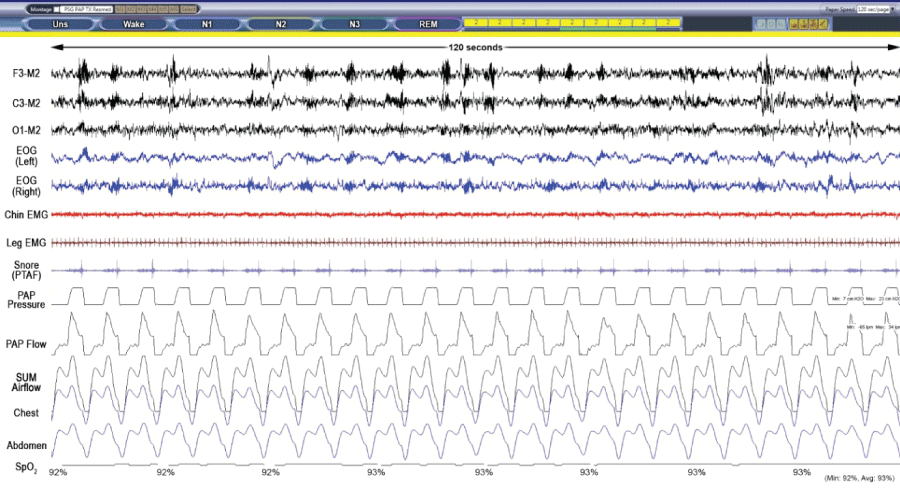

Figure 3B: VAPS Polysomnogram raw data breathing room air (120 s).

Screenshot obtained during Stage N2 while breathing room air and EPAP 8 cm H2O. The SpO2 measured 92% and the respiratory rate was 12/min.